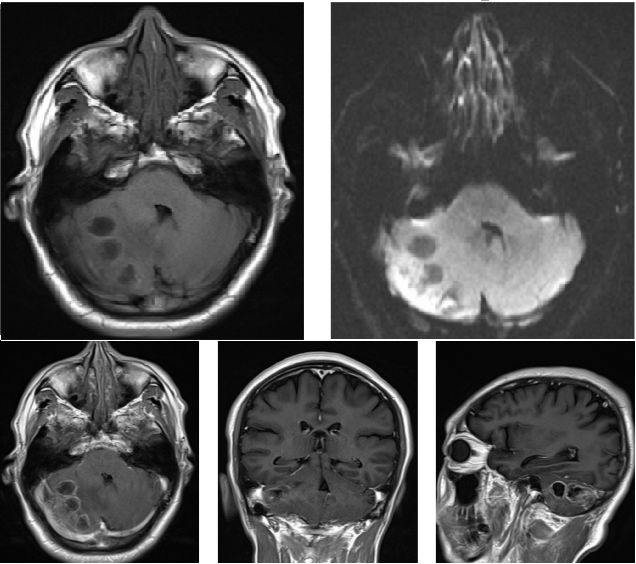

继续抗感染治疗10天,复查头颅MRI提示右侧小脑占位病灶较前增大(图4),提示抗生素对病灶无明显疗效,且血象、CRP、脑脊液相关检查均不支持感染性病变,倾向考虑肿瘤性质病变可能大。排除手术禁忌后,在全麻下行右侧小脑半球病变切除术,术中见病灶为肿瘤,位于右侧小脑半球,色红,质地软,与周围脑组织分界不清,血供丰富,中间伴囊性变,囊液清,呈浅黄色。取少量肿瘤组织(图5),送冰冻提示:小细胞恶性肿瘤,髓母细胞瘤可能。肿瘤予显微镜下全切。术后患者恢复良好,复查头颅MRI提示肿瘤全切(图6),术后一周顺利出院,至放化疗科进一步治疗。

图4. 小脑半球见团片状不均匀长T1长T2信号影,增强扫描可见环形强化,DWI病灶周边轻度受限,周围可见水肿带,占位效应可见,四脑室受压。